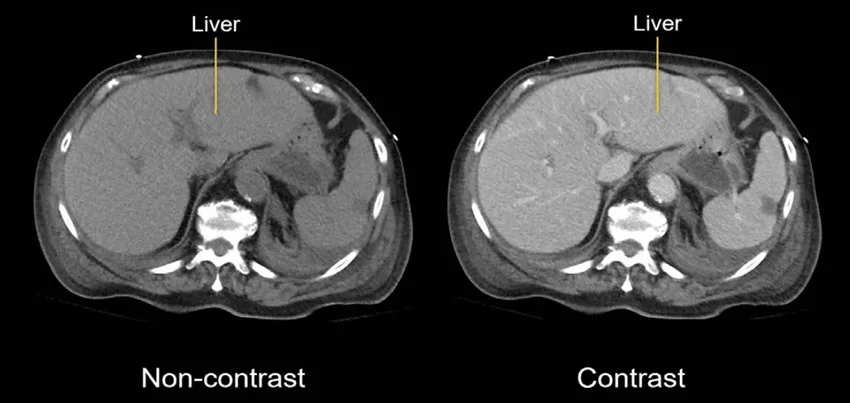

Contrast in CT scans refers to a substance, typically iodine-based, that is administered intravenously to enhance the visibility of blood vessels, organs, and tissues on imaging. Contrast helps differentiate between normal and abnormal structures, improving the accuracy of diagnosis and assessment.

Before the scan, patients may be asked to fast for a few hours to ensure optimal imaging quality. Once in the CT scanner, a contrast agent is injected intravenously, followed by sequential imaging of the abdomen. The contrast material highlights blood vessels and enhances the visualization of organs and tissues, providing detailed images for interpretation by radiologists.

Improved Visualization: Contrast enhances the visibility of blood vessels, organs, and abnormalities, allowing for more accurate diagnosis and assessment.

Enhanced Diagnostic Accuracy: The use of contrast helps differentiate between normal and abnormal structures, aiding in the detection and characterization of various conditions.

Radiologists interpret the images obtained from abdominal CT scans with contrast, analyzing the size, shape, density, and enhancement patterns of various structures. They look for signs of abnormalities, such as tumors, cysts, inflammation, or bleeding, and provide a detailed report to the referring physician for further evaluation and management.